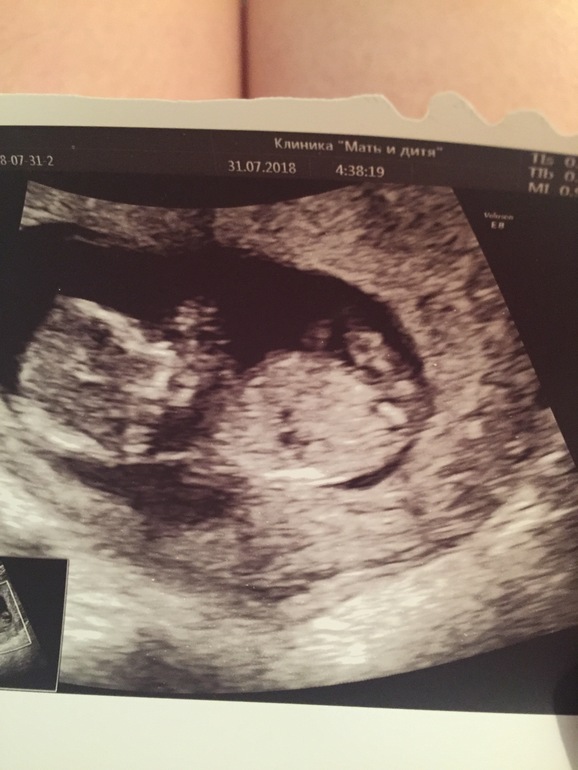

Делала в 12 тоже в мать и дитя, сказали девочка, в 16 подтвердили)

В 12 недель пол определяют по углу пипирки, у мальчиков торчком, у девочек угол меньше, где-то 30°. На фото вообще не видно пипки

Про пол на первом скрининге Всем доброго дня.